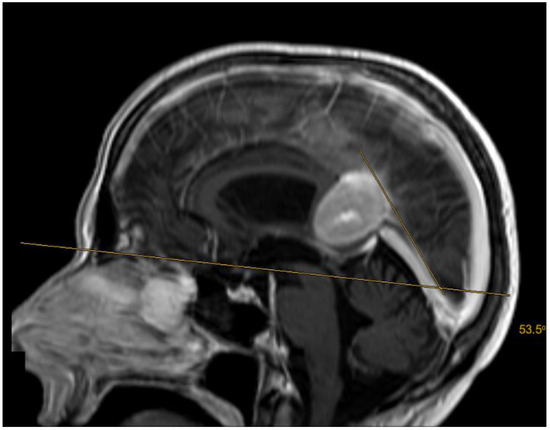

2.2. Volumetric Analysis, Vascular Features, and Tentorial Angle

| Tentorial angle | 49.6 (±6.2) | |